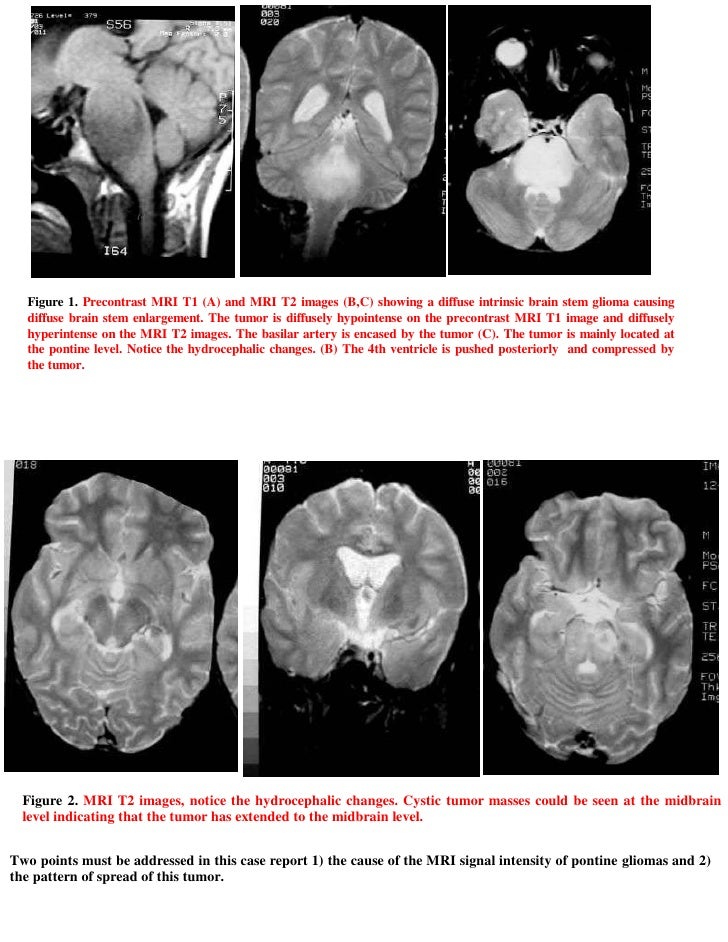

Short case...brain stem glioma

Short case...brain stem glioma from image.slidesharecdn.com